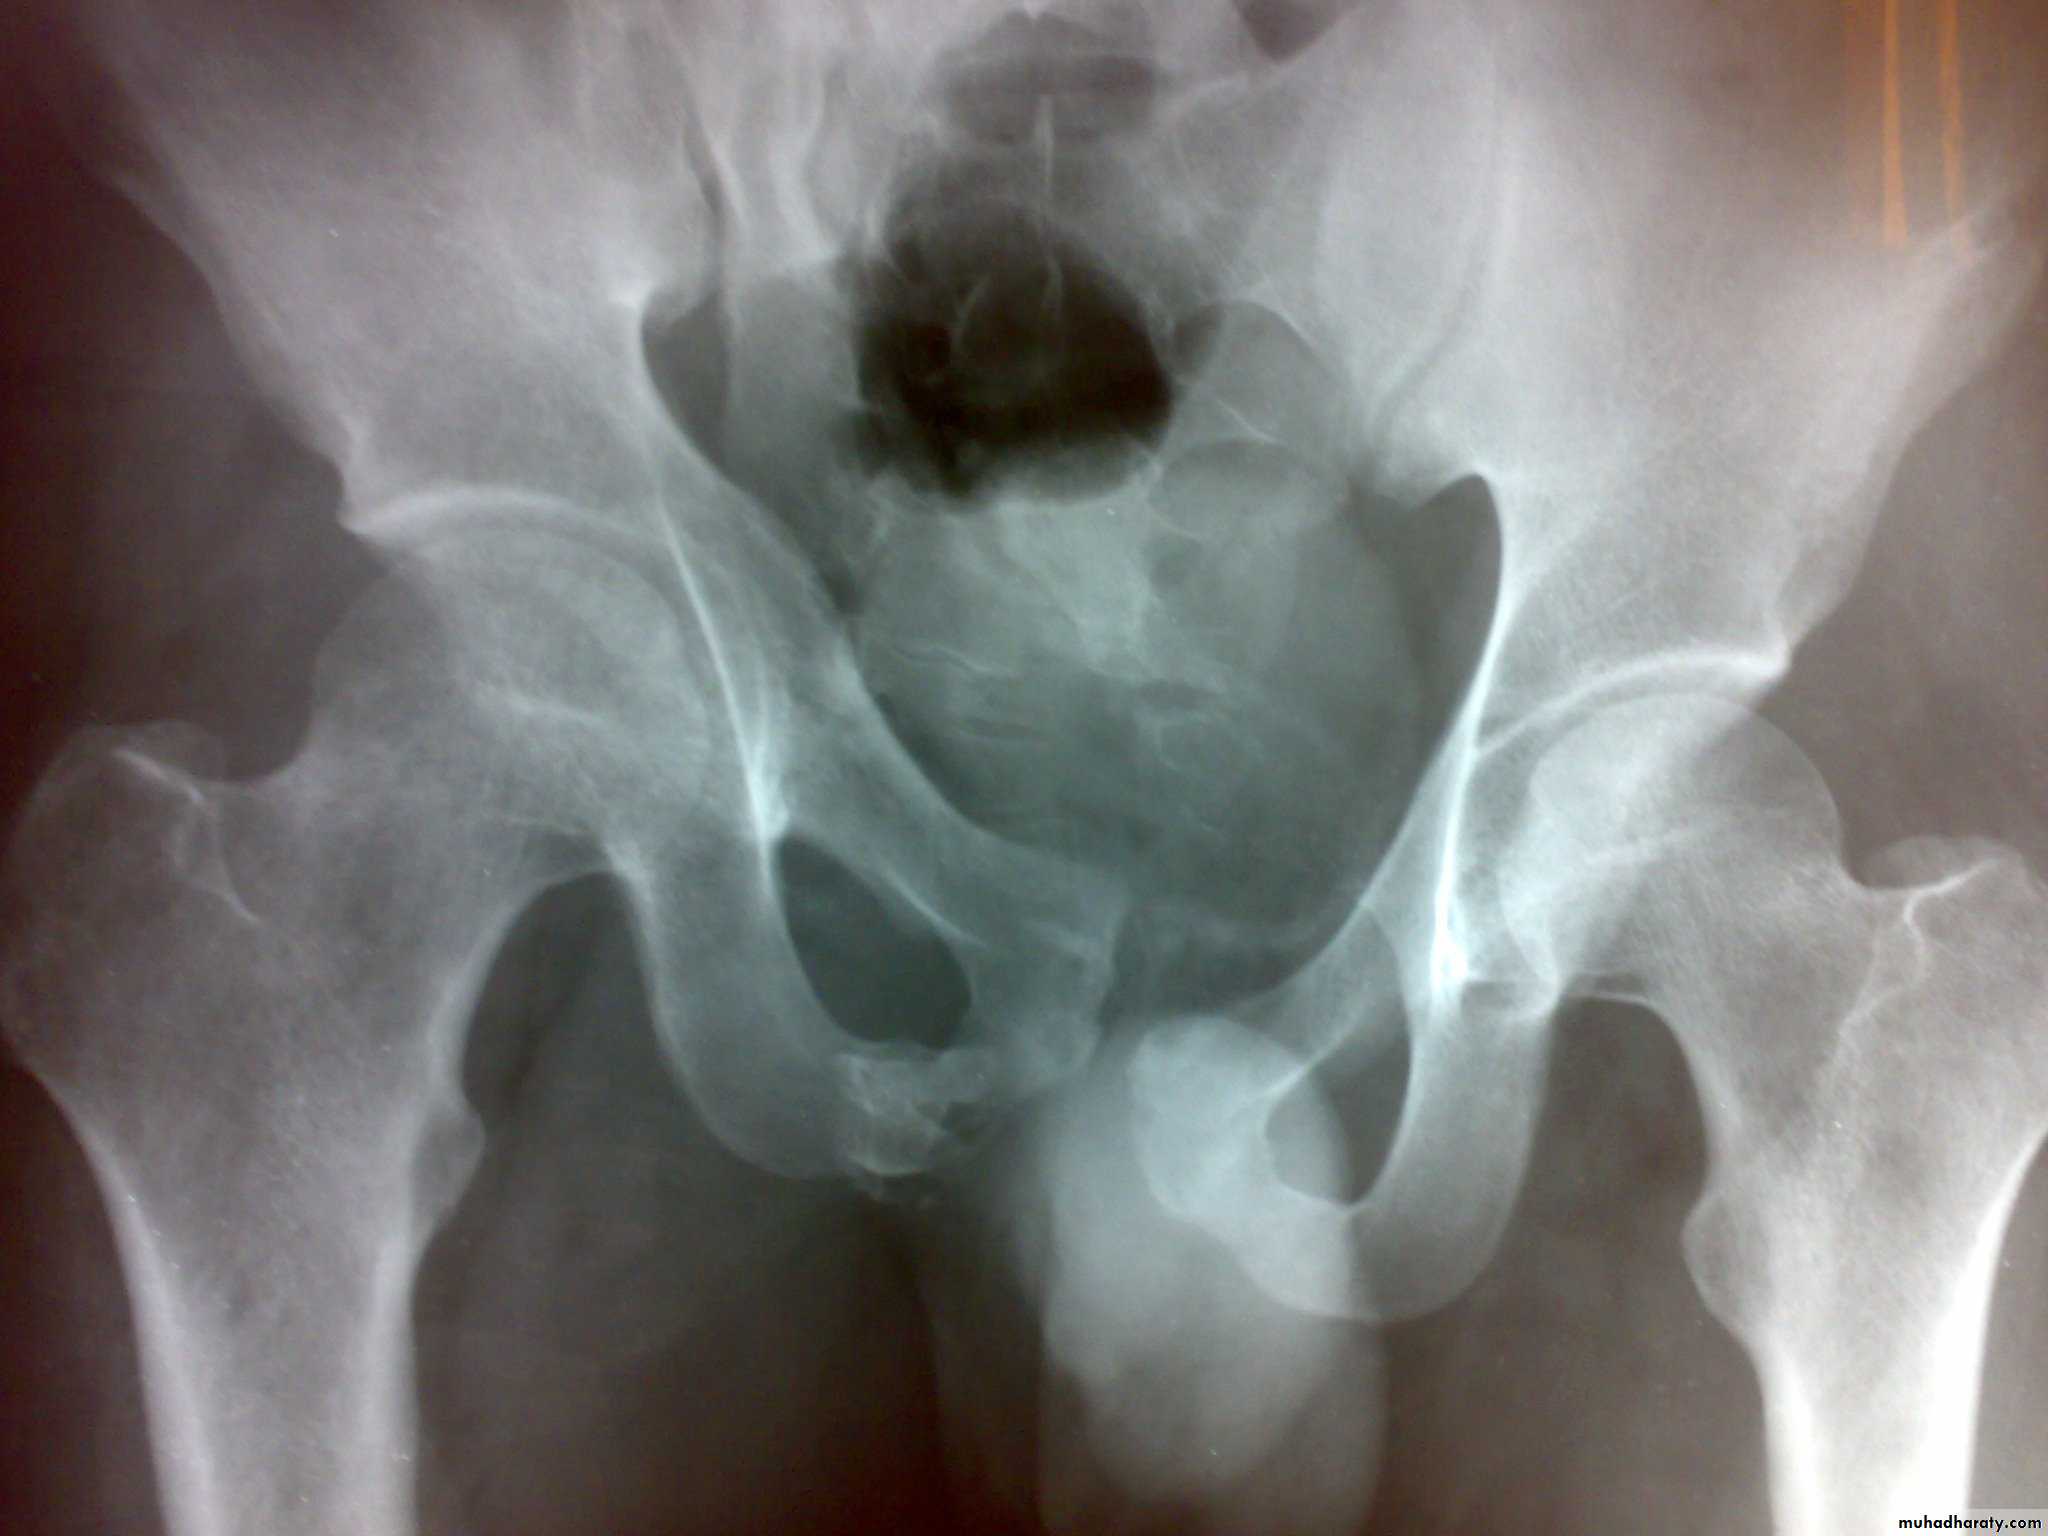

Unstable ring fractures

Caused by sever trauma.Extremely serious.

Carries high risk of visceral injuries.

There are fractures around or separation of symphysis pubis or sacroiliac joint.

Types of unstable fracture pelvic ring

1- antero-posterior compression (open book).

2- lateral compression (closed book).

3- Vertical force cause vertical displacement of the innominate bone on the same side.

4- combination injuries.